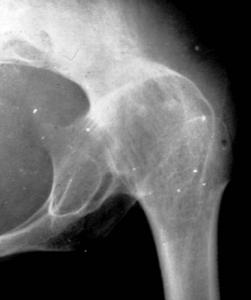

局限性骨脓肿是骨髓炎的另一种表现又称Brodie’s脓肿,急性化脓性骨髓炎后由于身体抵抗力强,细菌毒性低,但局部病灶完全消灭,残留在干骺端中心,使之局限化而不向周围扩散,病灶周围形成圆形骨硬化带。多发生于青壮年,多见于胫骨上端,股骨下端和上端、肱骨上端等长骨两端。